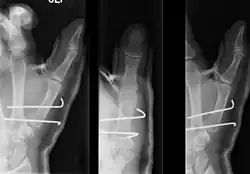

- For Bennett fractures where there is between 1 mm and 3 mm of displacement at the trapeziometacarpal joint, closed reduction and percutaneous pin fixation (CRPP) with Kirschner wires is often sufficient to ensure a satisfactory functional outcome. The wires are not employed to connect the two fracture fragments together, but rather to secure the first or second metacarpal to the trapezium.

- For Bennett fractures where there is more than 3 mm of displacement at the trapeziometacarpal joint, open reduction and internal fixation (ORIF) is typically recommended.